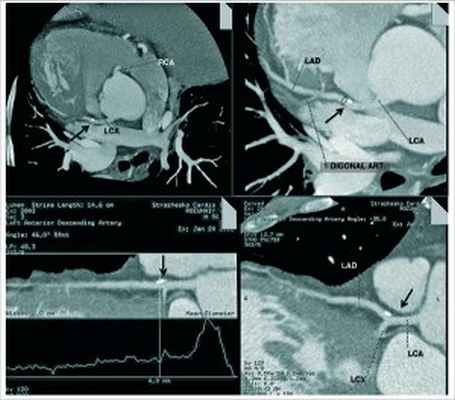

Учитывая неангинальный тип боли за грудиной, мужской пол и возраст пациента, претестовая вероятность ИБС у больного составила 44%, что требовало проведения дальнейшего неинвазивного обследования для верификации или исключения ИБС. У пациента невозможно было провести нагрузочный ЭКГ-тест (признаки гипертрофии ЛЖ на ЭКГ и депрессия сегмента ST в покое) и стресс-ЭхоКГ (неудовлетворительное акустическое окно), поэтому для данной цели использовалась КТ сердца с контрастированием коронарных артерий. Метод КТ является предпочтительным для постановки окончательного диагноза при транспозиции органов с декстрокардией, обеспечивает хорошую анатомическую детализацию расположения висцеральных органов, положение верхушки сердца и отхождение магистральных сосудов [15].

При мультиспиральной КТ-коронарографии сердце и крупные сосуды являются зеркальным отражением их нормальной анатомии; обнаружены признаки начальных атеросклеротических изменений коронарных артерий и локального кальциноза (единичная стабильная коронарная бляшка) (рис. 6). В проксимальном сегменте передней межжелудочковой ветви (ПМЖВ) левой коронарной артерии (ЛКА) атеросклеротическая бляшка без признаков гемодинамически значимого стеноза – 20% (рис. 7). Полости сердца – без особенностей (рис. 8). Транспозиция внутренних органов (рис. 9). Левая половина грудной клетки содержит трехдолевое легкое, правая половина грудной клетки – две доли легкого; печень и желчный пузырь находятся в левой половине брюшной полости, селезенка и желудок – справа. Частичный ателектаз средней доли левого легкого и сегментов S7, S8. Жировой гепатоз. Расширение восходящего отдела аорты.

Рис. 7. КТ-изображения ПМЖВ ЛКА (МСКТ2

постпроцессинговая обработка). КТ-признаки локального кальциноза в проксимальном сегменте ПМЖВ ЛКА, без гемодинамически значимого стеноза на указанном уровне (стрелка)